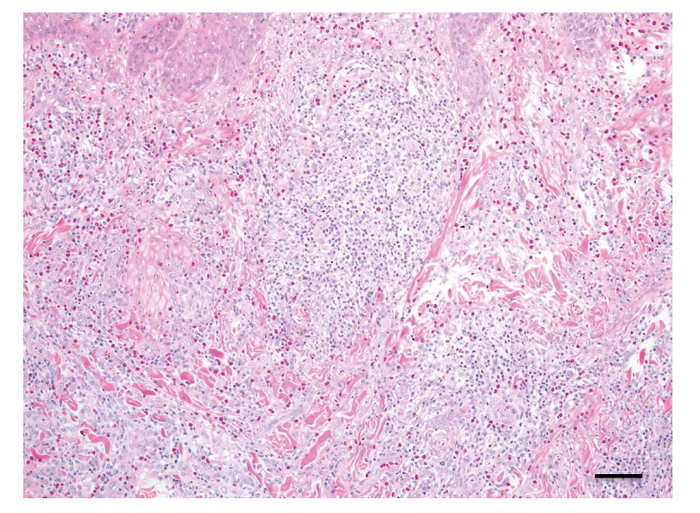

这种由异物入侵的造成的囊肿在医学上叫“异物肉芽肿”[16],不过以蚊子的口器直径(30微米)和形状(一根光滑的尖刺)来看[17][18],这种肉芽肿的发生概率极小,即使真的发生了,它基本上也会随着皮肤本身的新陈代谢和血液供应不足而消失[19],或者被身体自身的酶吃掉[9]。恢复时间和异物大小也就是损伤程度直接相关。

图为真皮内可见的淋巴细胞、嗜酸性粒细胞、浆细胞及组织细胞组成的混合细胞肉芽肿显微结构 / [18]